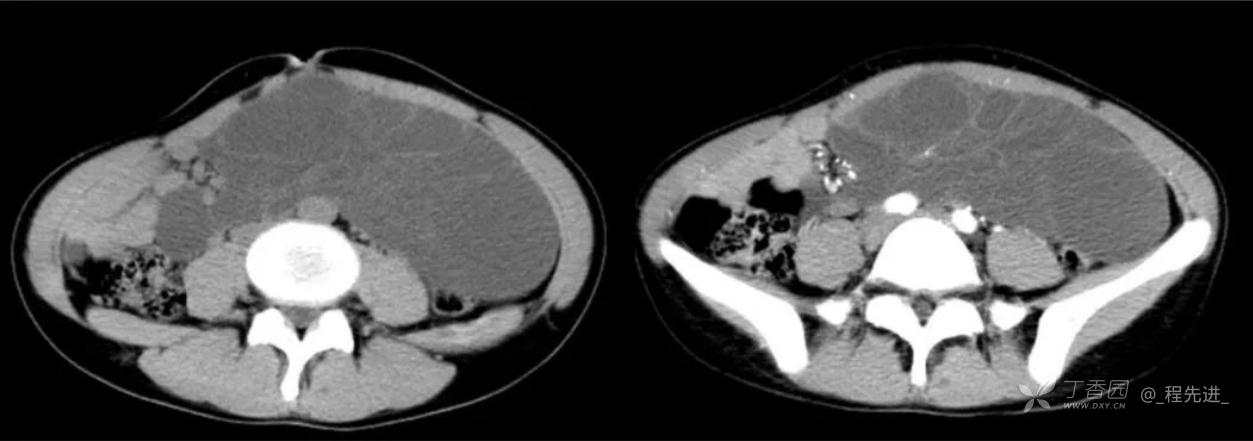

患者性别:女

患者年龄:24岁

主诉:腹痛、发热一天

现病史:一天前无明显诱因出现腹痛并发热不适,伴恶心、干呕,诊所肌注药物(具体用药不详),无缓解,无明显尿频、尿痛。

体格检查:腹肌稍紧张,右上腹部轻压痛,右肾区叩痛